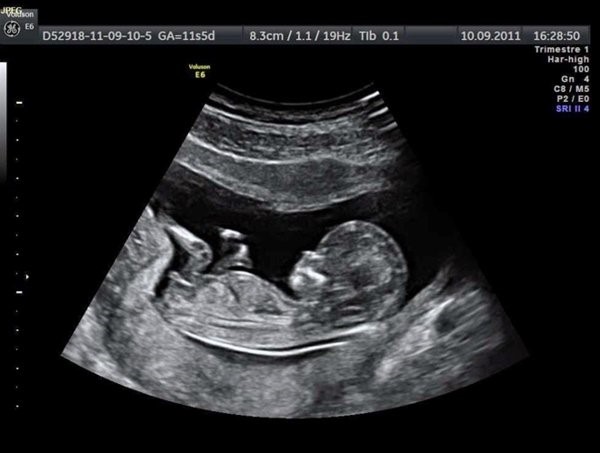

Điều thắc mắc lớn nhất của nhiều chị em khi thực hiện siêu âm thai 5 tuần tuổi đó là mẹ sẽ thấy gì. Tuy hình ảnh qua các thiết bị có thể không rõ nét nhưng một số thay đổi đã bắt đầu xuất hiện trên phôi thai mà bác sĩ có thể thấy được như:

– Phôi thai và tim thai: Ở một số bà mẹ có phôi thai phát triển nhanh thì đã có thể thấy được tim thai khi siêu âm thai 5 tuần tuổi.

– Túi noãn hoàng: Khi siêu âm vào giai đoạn này thì có thể bác sĩ sẽ thấy được túi noãn hoàng của thai.

– Túi thai: Túi thai là bộ phận có chức năng bao bọc thai nhi và nước ối. Vì thế khi siêu âm thai 5 tuần tuổi, mẹ sẽ có thể nhìn thấy được túi thai một cách rõ nét.